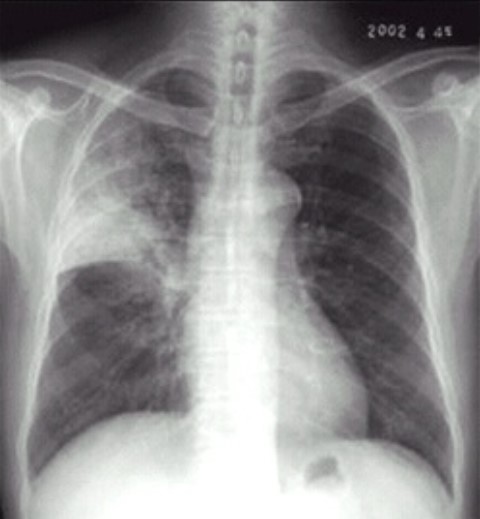

02卷-4.男性,24歲,發(fā)熱、咳嗽、咳痰4天。診斷

A.右上肺不張

B.右上胸膜肥厚

C.右上肺癌

D.右上肺炎

本題答案:D

【該題針對“ X線-肺炎 ”知識點(diǎn)進(jìn)行考核】